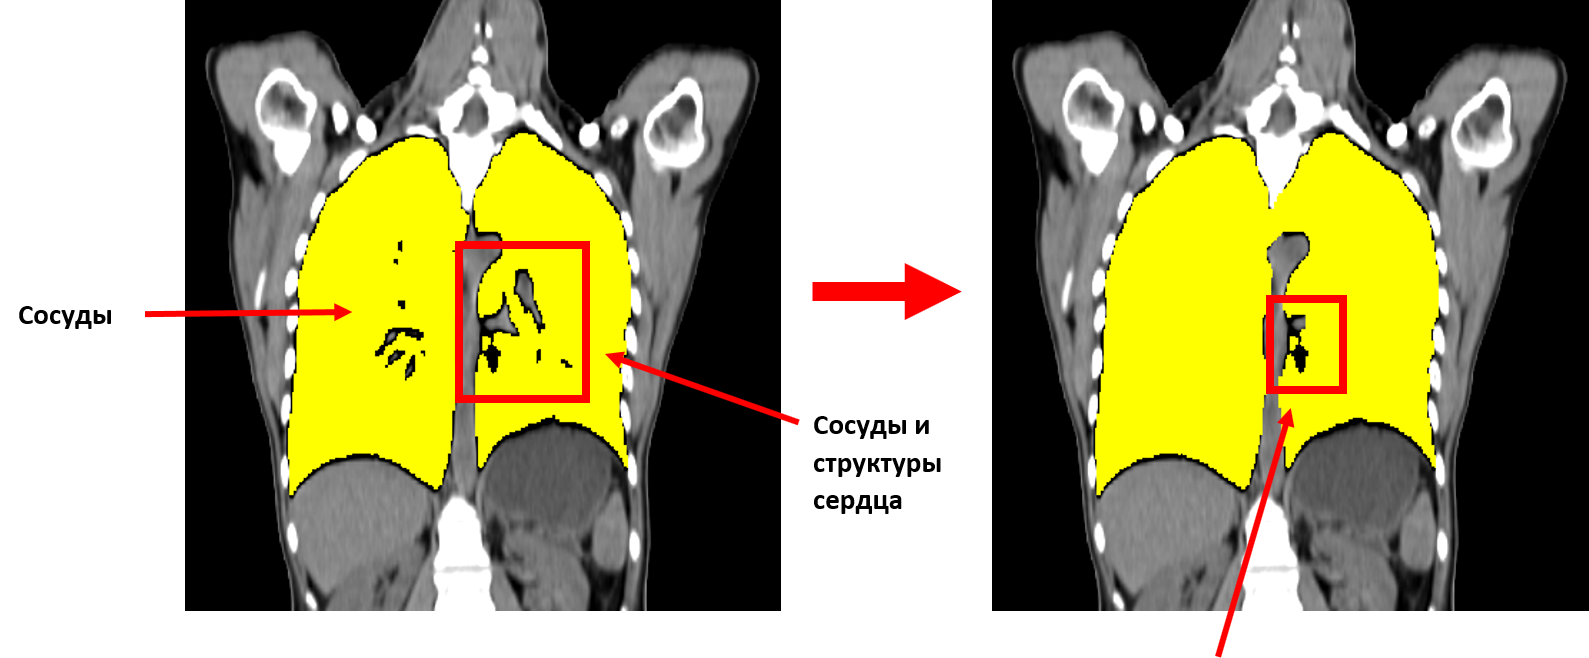

Для захвата сосудов внутри лёгких применим морфологическое закрытие, то есть дилатацию с последующей эрозией с тем же радиусом. Рентгеновская плотность сосудов составляет около -100..100 HU.

Крупные кровеносные пути не закрылись. Но в этом и нет необходимости. Цель данной операции была в уничтожении множества мелких отверстий внутри легких для упрощения дальнейшей сегментации легких.